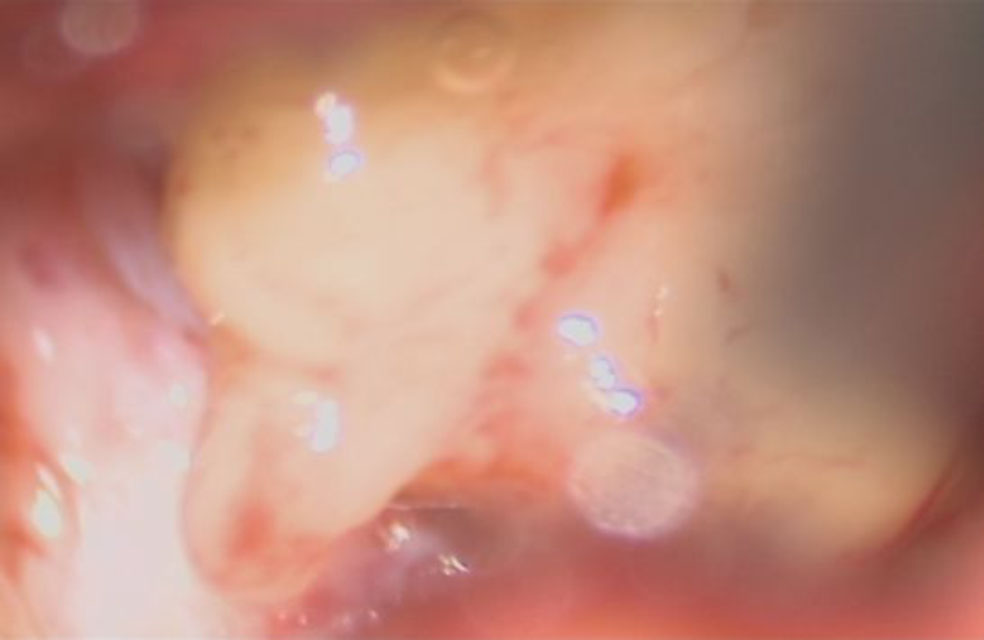

摘出 後

No.’25_108 摘出 後